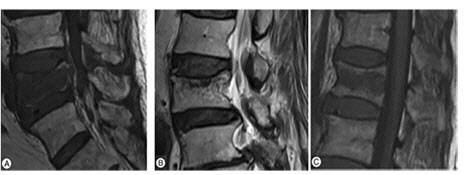

가톨릭대학교 서울성모병원 정형외과 김영훈(교신저자) 교수팀이 골다공증성 척추 골절 환자가 수술로 이행될 수 있는 위험요인, 즉 예측인자를 확인하기 위해, 골다공증성 흉요추 척추골절 환자를 조사하였다. 우선적으로 보존적 치료를 시행했으나, 척추 변형이나 신경학적 증상으로 결국 수술이 필요했던 환자를 제1군, 보존적 치료로 성공적으로 치유된 환자를 제2군으로 나누어, 척추 X선 사진과 MRI 검사 소견을 비교했다.

또한, MRI에서는 척추뼈의 위아래 가장자리 끝에 골절이 있는 ‘종판타입’이 제2군에서 높은 비율을 차지하고 있음을 보고하여, 종판타입에서 보존적 치료가 성공적으로 마무리 될 가능성이 높음을 재확인했다.